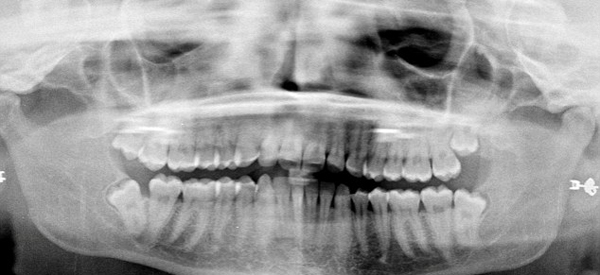

Удаляя зуб мудрости, стоматолог случайно оторвал пациентке кусок щеки и нижней губы

Во время удаления зуба мудрости, стоматолог упустил щипцы и оторвал пациентке кусок щеки и нижней губы - размером 7 см х 5,5 см.

31-летней пациентке МакЭван пришлось накладывать швы, чтобы зашить рану.

Пациентка обратилась в стоматологическую клинику в городе Уотфорд, Англия, по рекомендации, чтобы ей удалили два зуба мудрости. Но получила четыра шва, две недели сильной ушной и головной боли и онемевшую левую сторону лица, так как был задет нерв.

Несмотря на то, что стоматолог отрицает свою вину, пациентка получила компенсацию в размере 22000 фунтов благодаря помощи компании по защите прав пациентов стоматологических клиник Dental Law Partnership.